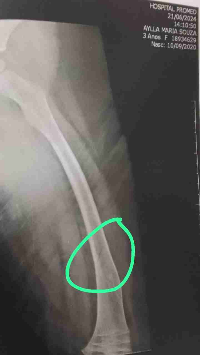

Ela nasceu com

Osteogênese Imperfeita, uma doença rara que torna seus ossos extremamente frágeis. Fazemos tratamento no Hospital das clínicas com o Dr. Frederico Barros, Ortopedista, e ela já faz o uso do medicamento Pamidronato há um ano.

Aos 4 aninhos, Aylla já sofreu 10 fraturas decorrentes da doença.